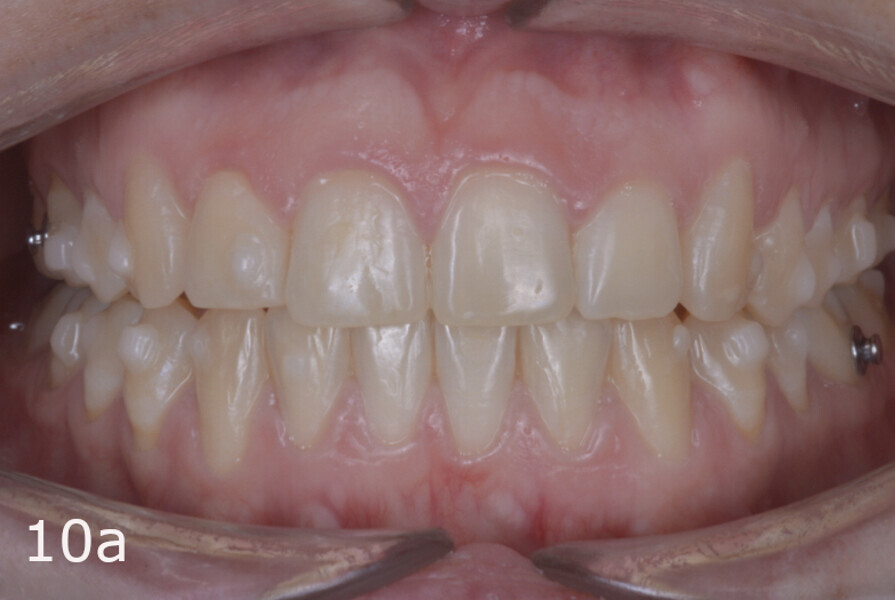

The treatment objectives included closing the anterior open bite, achieving a bilateral Angle Class I relationship and a proper overjet and overbite, correcting the midline discrepancies, and achieving a profile harmonisation. The treatment plan consisted of orthodontic camouflage treatment with asymmetric distalisation in three of the four quadrants using Invisalign aligners (Align Technology) and third molar extraction. The Invisalign Comprehensive package was chosen, and 63 pairs of aligners were used (Figs. 7–10). Each aligner was worn for 20 hours a day for one week each. The use of Class III elastics on both sides was indicated. Afterwards, ten refinement aligners were needed to improve the interdigitation on the right side (Figs. 11 & 12).